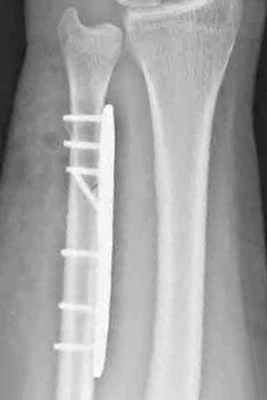

При переломах диафиза и метафиза обеих костей или изолированных переломах лучевой и локтевой костей остеосинтез производят прямыми узкими, желобоватыми пластинами.

Принципы экстракортикального остеосинтеза костей предплечья.

Остеосинтез при переломах дистального отдела лучевой кости производят редко, как правило, при неудаче консервативного лечения. Для остеосинтеза применяют малую Т-образную пластину (Рис. 140).

Остеосинтез лучевой кости в дистальном отделе